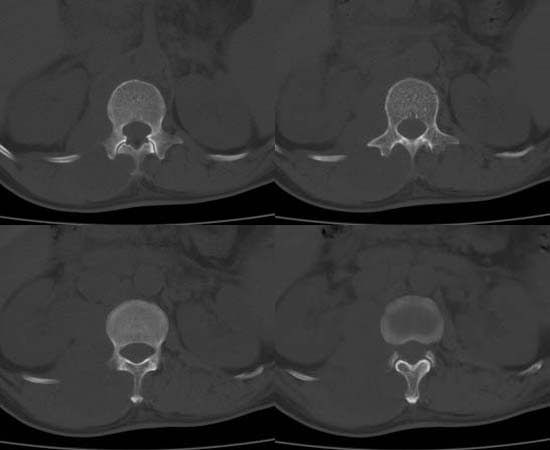

以下是引用刘明在2007-6-26 16:00:00的发言:[br][br]右侧竖直肌及腰大肌肿胀,脂肪间隙难辨,腹膜后血管旁见多个肿大淋巴结影,椎体附件右侧有压迫吸收、未见硬化迹象,考虑椎旁冷脓肿可能[br]左侧肾盂内可见高密度影,周围有毛刺,本图象是平扫,不是增强,应该是结石[br]

以下是引用hhcckk在2007-6-27 9:41:00的发言:[br]肾周筋膜增厚,胰腺影肥大,楼主是考我们了,我考虑是胰腺炎引起的腰部感染,形成的蓝棕色斑,也称gray-turner征,另外腹膜后怎么这么多的淋巴结,转移也要考虑[br]结核三个月没有骨破坏?寒性脓肿累及到竖脊肌的少见,所以我考虑结核的可能性不太大[br]左肾内高密度影,密度不太均匀,左肾有积水的表现,考虑是结石[br]期待楼主老师的结果